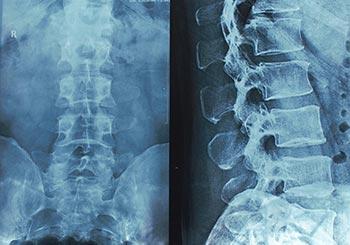

These are spinal X-rays to illustrate our post on spine surgery research.